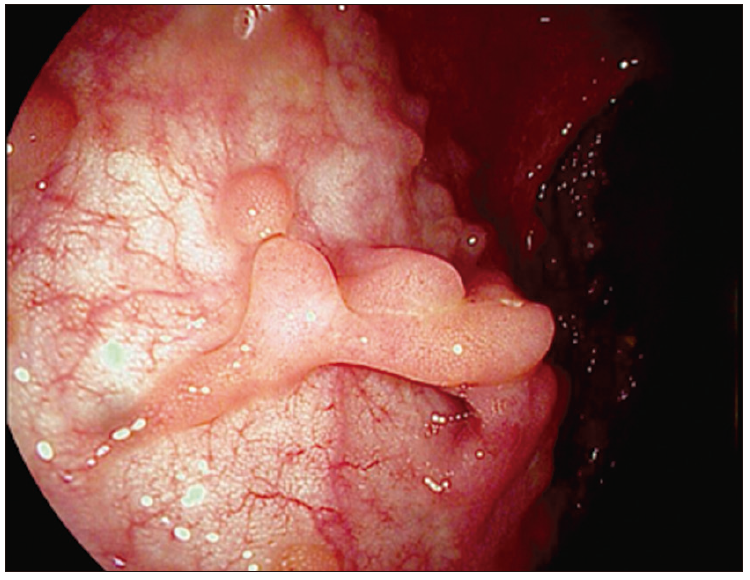

Foto 3. Pseudopólipos en colitis ulcerosa grave

Respuesta al tratamiento: frente a modificaciones de esquemas terapéuticos, la visualización directa aporta información objetivamente comparable de la respuesta y alcance de los objetivos deseados. En ocasiones el daño cicatrizal en forma de tractos lineales longitudinales o confluentes o la presencia de pólipos post inflamatorios (estructuras sésiles o digitiformes con superficie y coloración similar a la mucosa circundante) hacen evidente el daño previo, impidiendo el retorno de la mucosa a la normalidad pero evidenciando hallazgos secuelares no activos.

Curación mucosa: la confirmación del control de la actividad inflamatoria a nivel mucoso se ha posicionado como objetivo terapéutico, ya que representa un parámetro objetivo que permite equilibrar la toma de decisiones estratégicas, identificando pacientes en riesgo de progresión de la enfermedad, subtratados con enfermedad activa oligosintomática, de pacientes en riesgo de eventos adversos asociados al sobretratamiento innecesario. La curación mucosa está asociada a una disminución significativa del riesgo de recaídas, hospitalizaciones y cirugías.70

Foto 4. Pólipos post inflamatorios en CU en remisión con patrón vascular

conservado